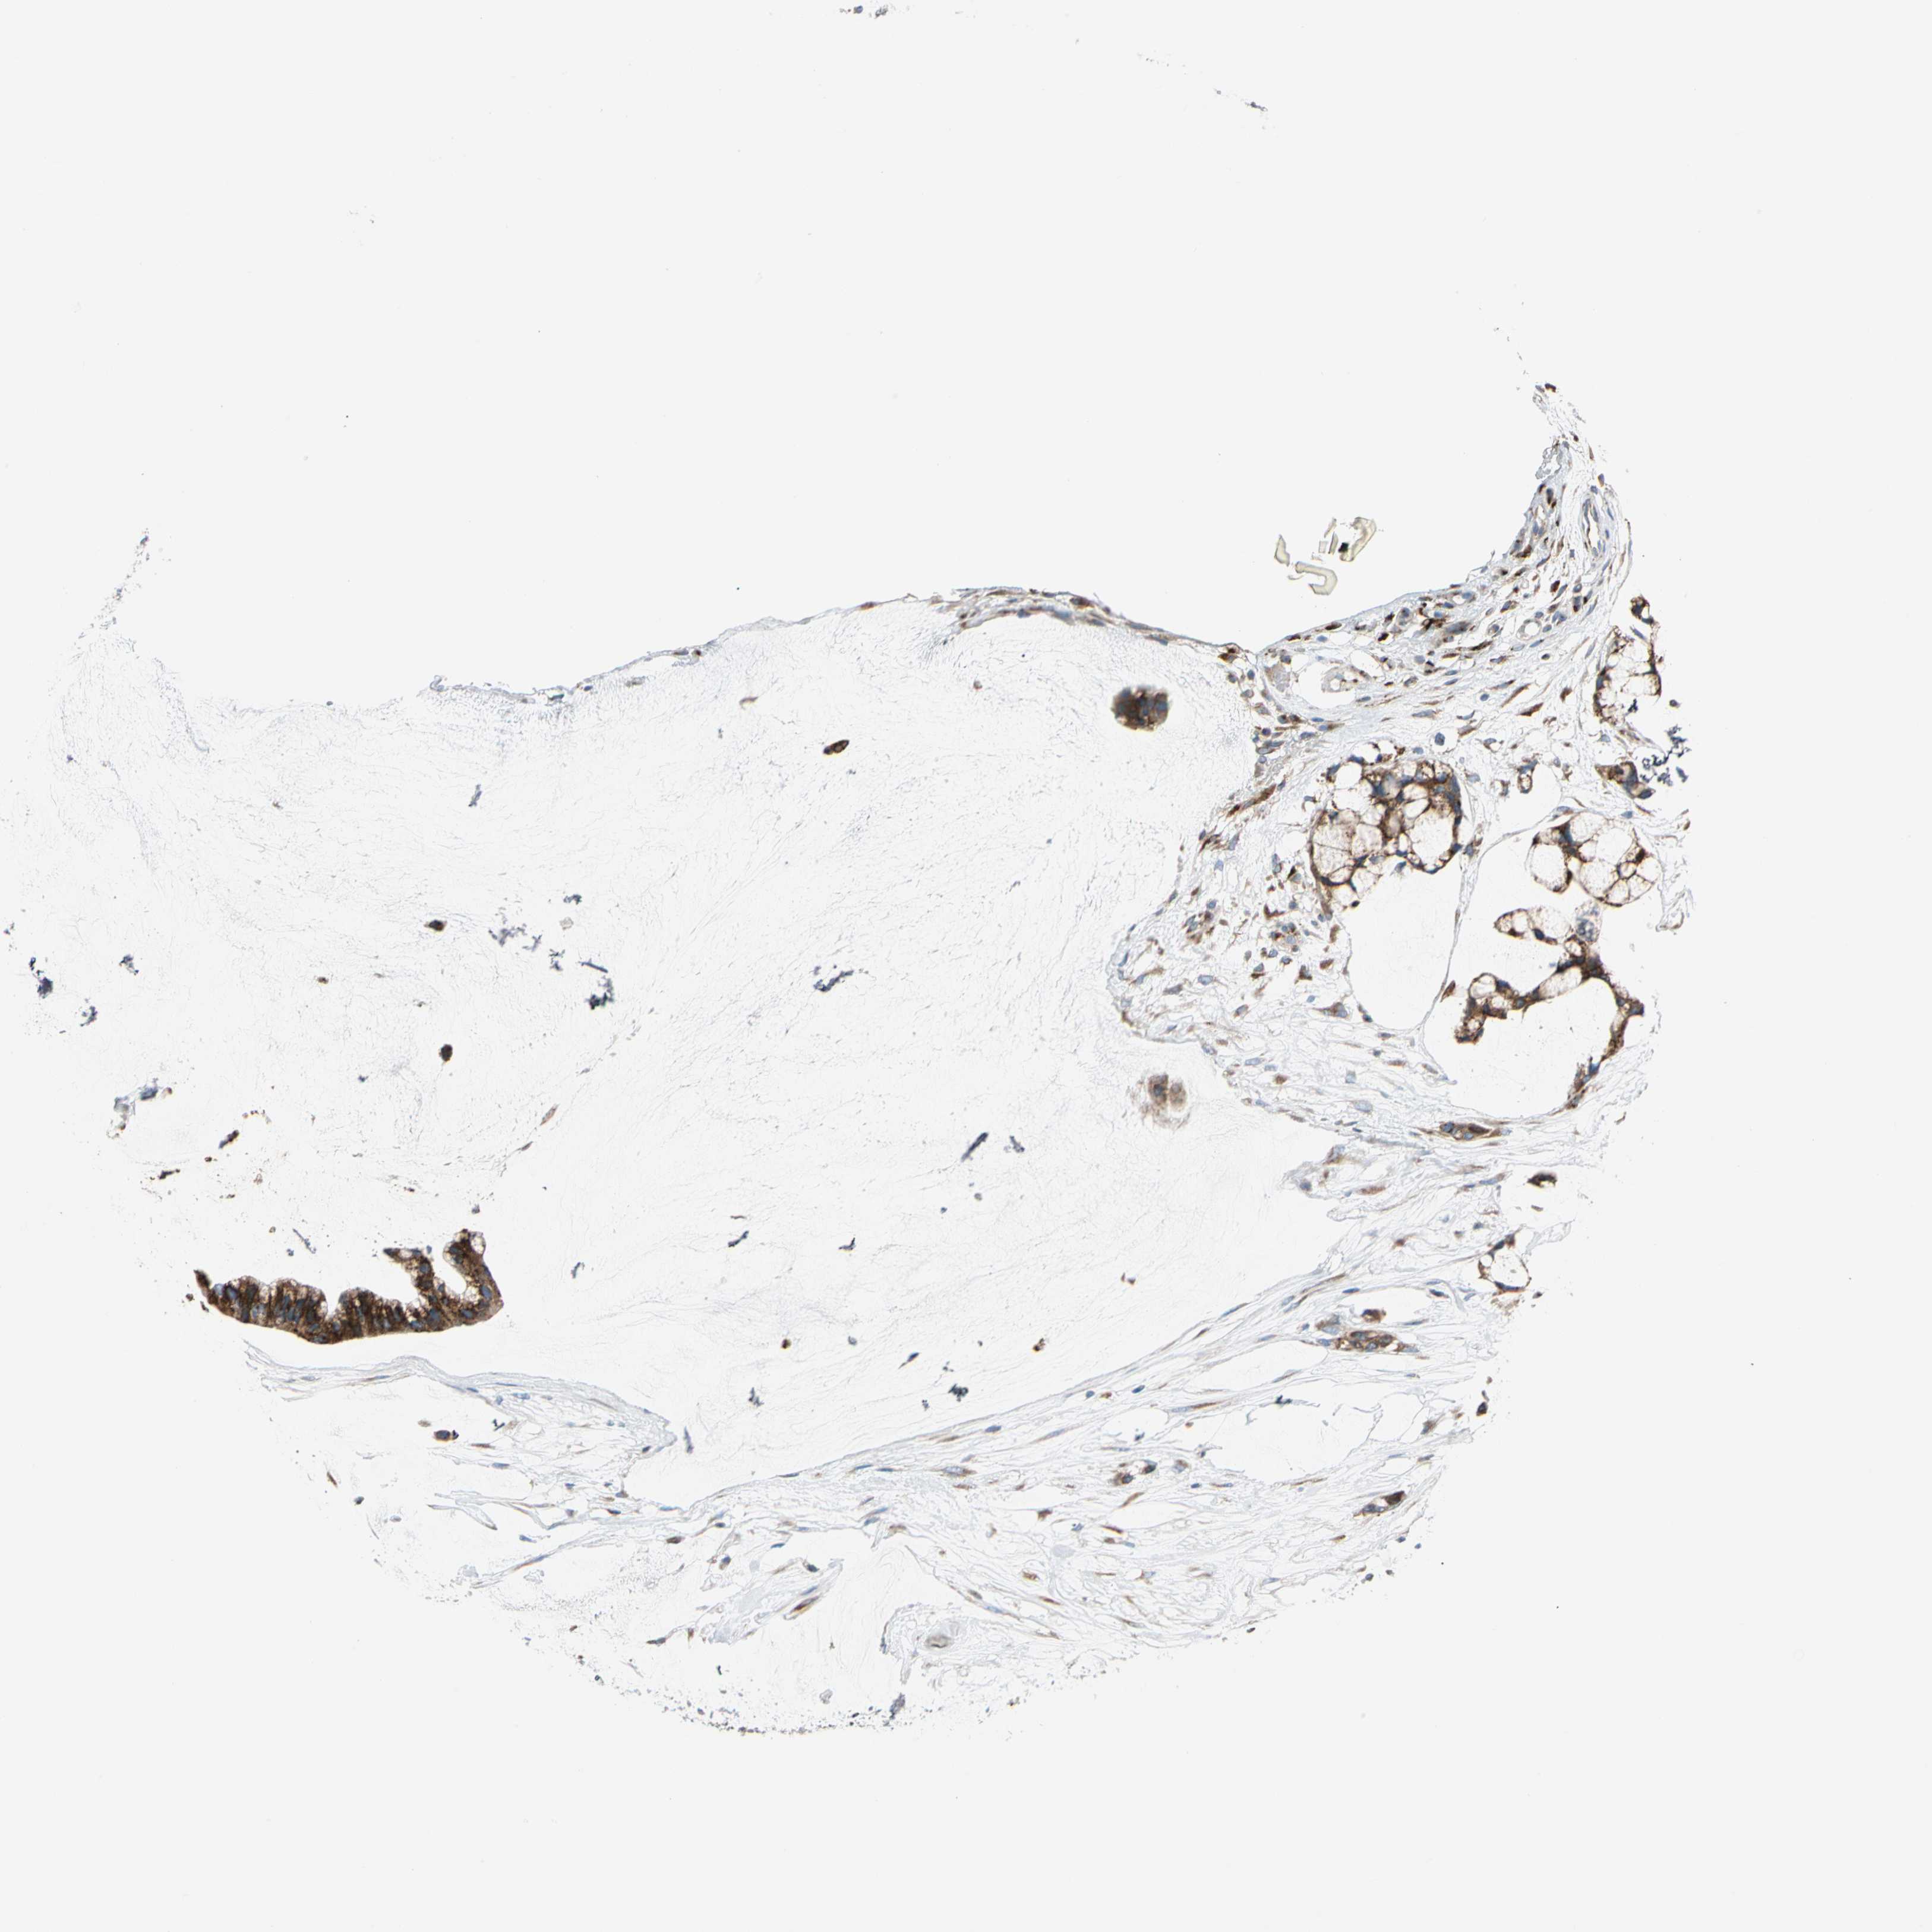

OVARIAN CANCER - Protein expressioni

A mouse-over function shows sample information and annotation data. Click on an image to view it in a full screen mode. Samples can be filtered based on level of antibody staining by selecting one or several of the following categories: high, medium, low and not detected. The assay and annotation is described here.

Note that samples used for immunohistochemistry by the Human Protein Atlas do not correspond to samples in the TCGA dataset.

Antibody stainingi

Antibody staining in the annotated cell types in the current human tissue is reported as not detected, low, medium, or high, based on conventional immunohistochemistry profiling in selected tissues. This score is based on the combination of the staining intensity and fraction of stained cells.

Each image is clickable and will lead to virtual microscopy that enables deeper exploration of all samples and also displays staining intensity scores, fraction scores and subcellular localization as well as patient and tissue information for each sample.

Antibody HPA008176

Staining

High

Medium

Low

Not detected

Intensity

Strong

Moderate

Weak

Negative

Quantity

>75%

75%-25%

<25%

None

Location

Nuclear

Cytoplasmic/membranous

Cytoplasmic/membranous,nuclear

Cystadenocarcinoma, serous, NOS

Carcinoma, endometroid

Cystadenocarcinoma, mucinous, NOS

Carcinoma, NOS